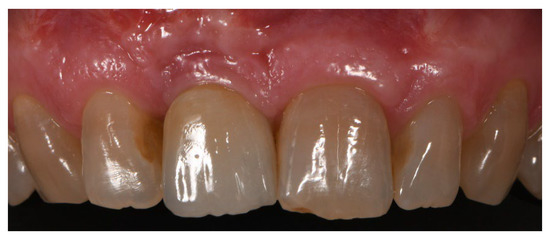

3. Results

3.1. Implant Failure, Complications, and Patients’ Satisfaction